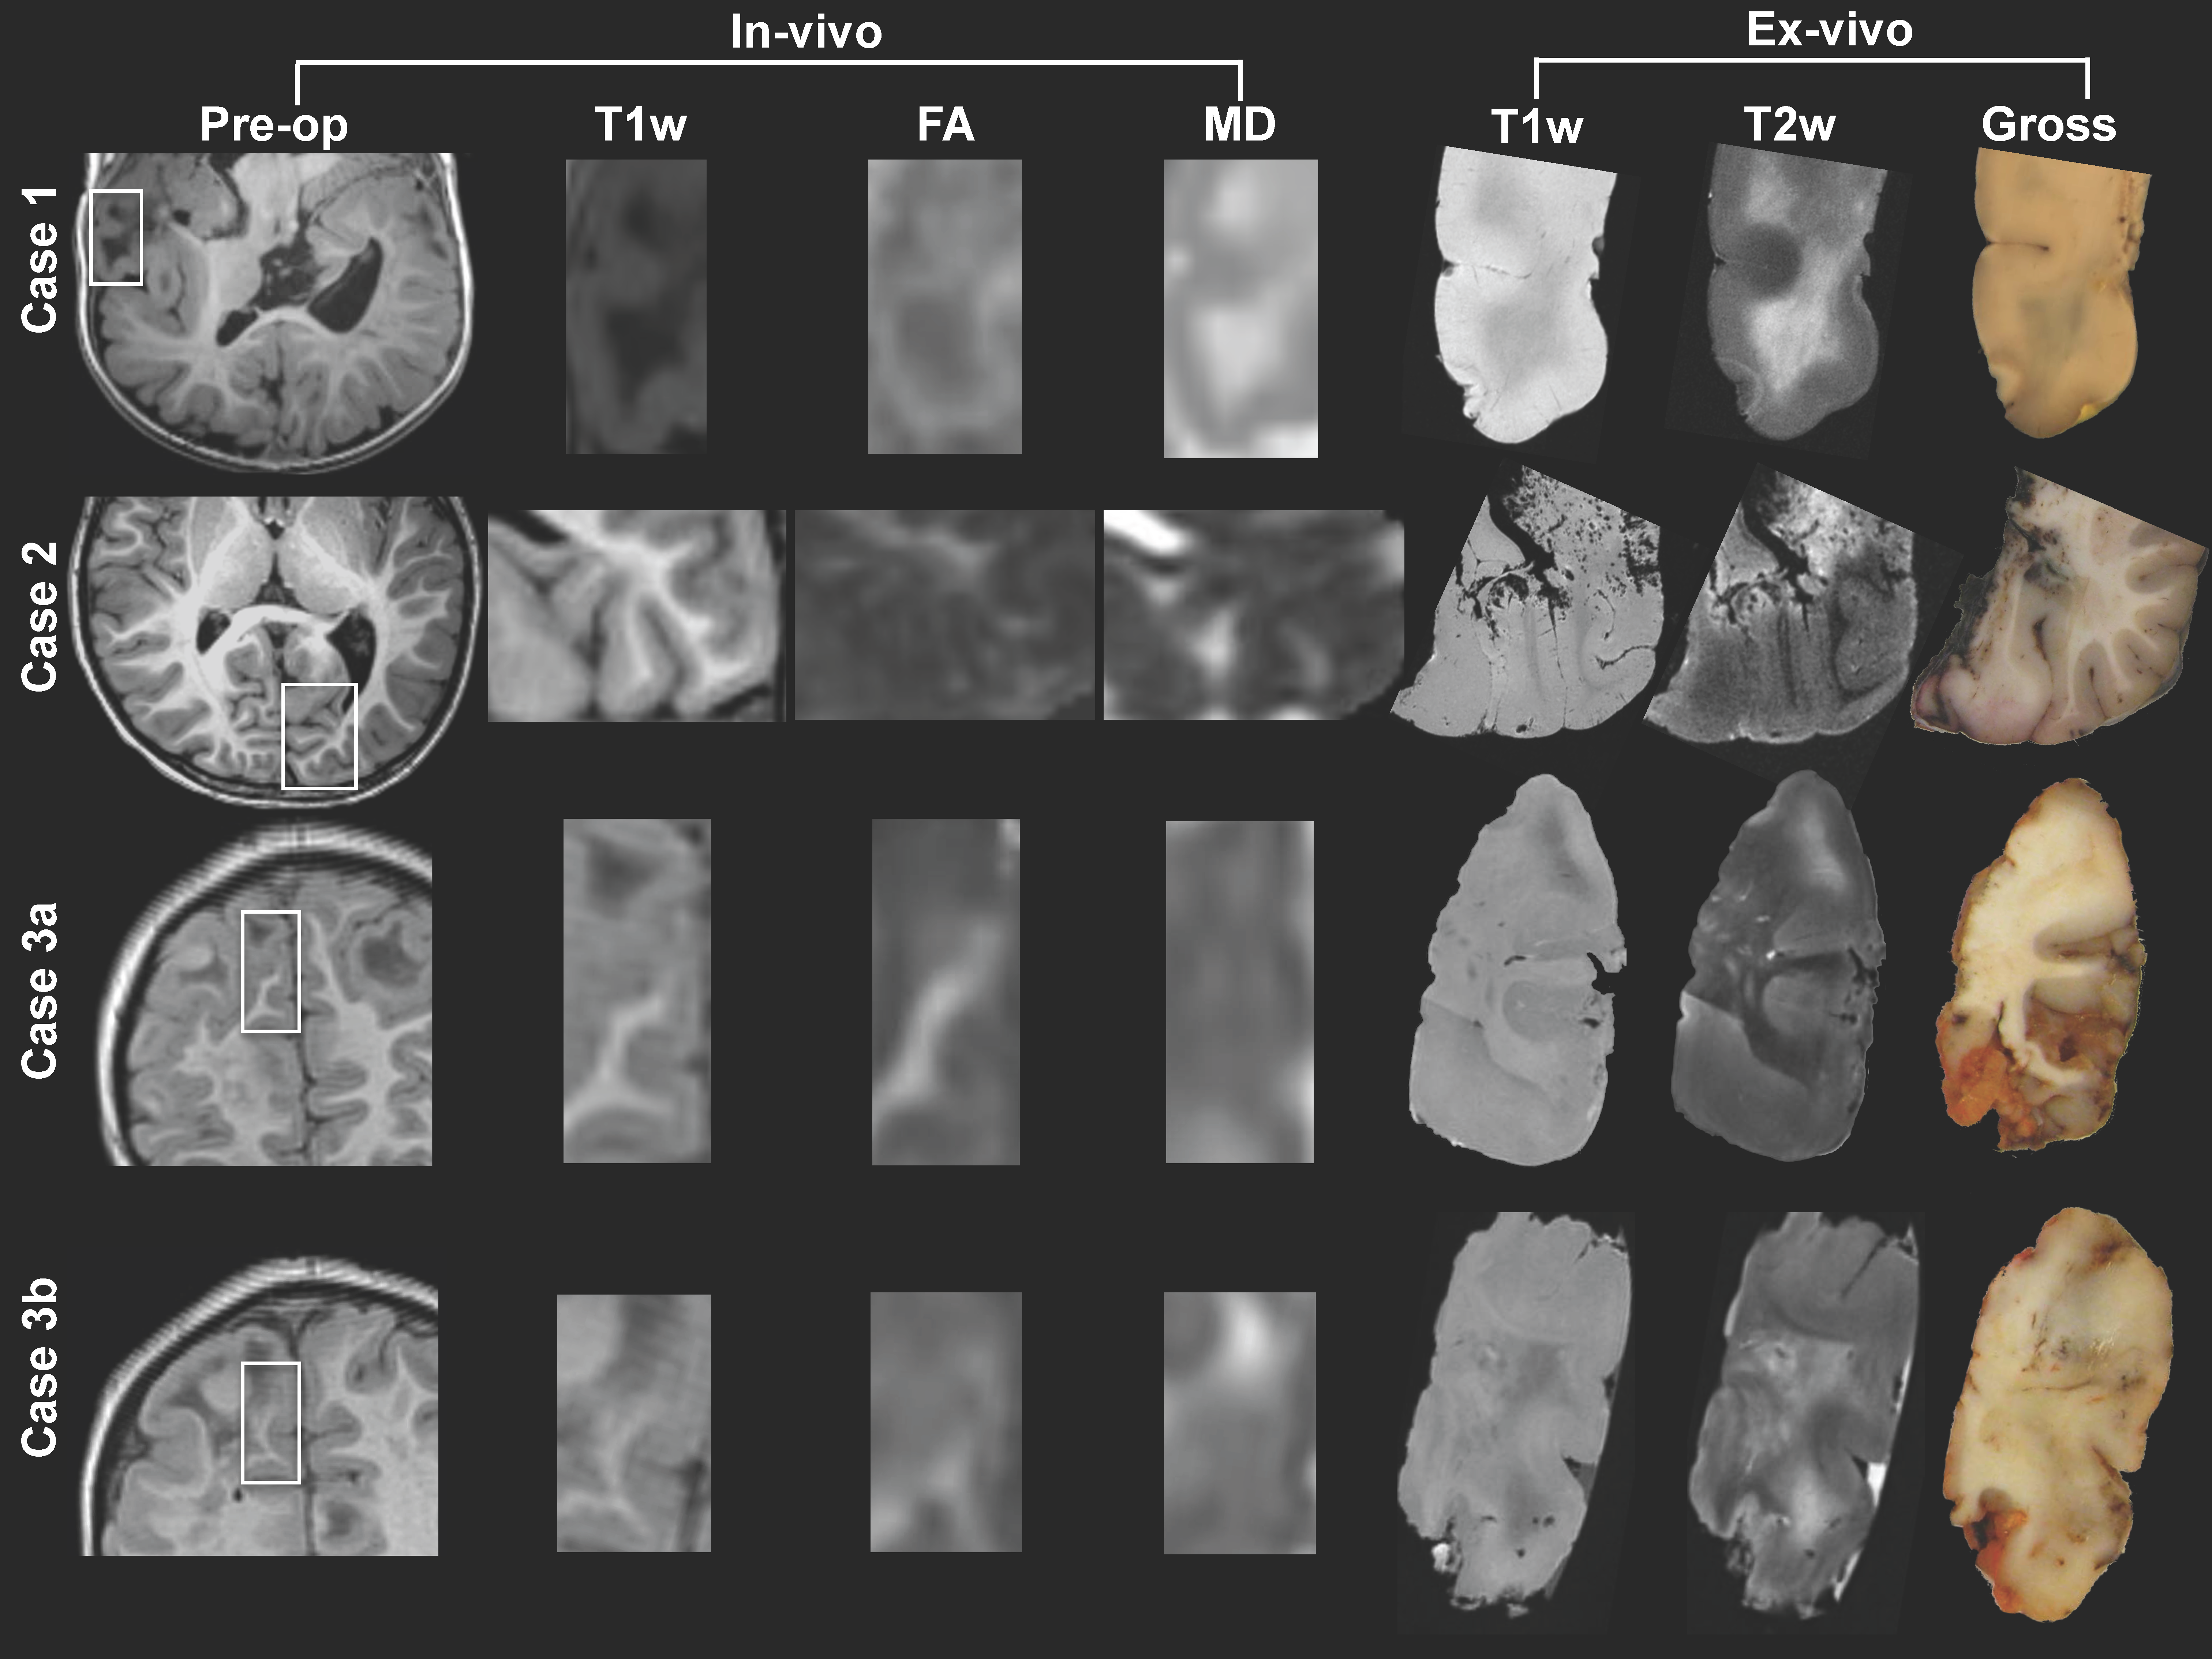

Rationale: To clarify the basis of abnormal diffusion in Tuberous Sclerosis Complex (TSC) in the proximity of epileptogenic tubers, we correlated ex vivo high-resolution diffusion imaging of white matter, perituber and tuber regions with histopathology. Methods: Three 'en-block' epilepsy surgical specimens from children with TSC were scanned in a 3T or 7T MRI with a structural image isotropic resolution of 137-300 micron, and diffusion image isotropic resolution of 270-1,000 micron. Next, we stained four specimens for myelin (luxol fast blue, LFB) and gliosis (glial fibrillary acidic protein, GFAP), and registered digitized slides (0.686 micron resolution) to high-resolution ex vivo MRI for histopathological comparison.Figure 1: Pre-operative imaging and orientation of resection specimens ex vivo.Resection regions are highlighted in the white rectangle in the preoperative images.  Magnified frames of T1-weighted (T1w), fractional anisotropy (FA) and mean diffusivity (MD) are shown, and compared to the ex vivo images on the right. Note that the imaging plane is manipulated to match the ex vivo cutting plane and histopathology slides; e.g. case 1 is a pseudo-axial plane, and images may be inverted along any axis.  Results: In white matter and perituber regions, LFB optical density (OD) correlated with fractional anisotropy (FA) and inversely with mean diffusivity (MD) and T2w intensity. In white matter but not perituber tissue, GFAP OD correlated with MD and T2w, and inversely with FA. In tubers and in the cortex, there  was little variation in mean LFB and GFAP signal intensity, and no correlation with MRI metrics.Figure 2: Example: Quantitative comparison of histopathology and ex vivo MRI for case 2(LEFT ) Luxol fast blue (LFB) stain, after color deconvolution. (RIGHT ) Glial fibrillary acidic protein (GFAP) stain, after color deconvolution.In the left column, ex vivo structural images (T1w, T2w) and diffusion imaging (fractional anisotropy FA, mean diffusivity MD). On the top row, the regions of interest (ROIs) are placed in specific ultrastructural tissue types: Cortex, tuber, perituber, and white matter. In the last column, two tissue types (perituber and white matter) are merged, yielding a wider variability. The colored dots indicate intensity histograms, and the hot colors indicate more overlap between MRI metrics and histopathology optical density values. Spearman’s Rho correlations are listed, and regression lines are shown for higher values. Conclusions: These findings suggest diffusion imaging abnormalities in microscopic tissue types correspond to specific histopathological markers in TSC. Funding: J. Peters, B. Scherrer, S. Prabhu, M. Sahin, and S. Warfield are supported by NIH R01 NS079788 and U01 NS082320 grants. A. Prohl is supported by Harvard Catalyst | The Harvard Clinical and Translational Science Center (National Center for Research Resources and the National Center for Advancing Translational Sciences, NIH award UL1 TR001102). S. Prabhu is also supported by the Department of Defense W81XWH-11-1-0365. M. Sahin is additionally supported by NIH U54 HD090255 and U54 HD090255 grants and the Boston Children’s Hospital Translational Research Program. The Developmental Synaptopathies Consortium (U54 NS092090) is part of the NCATS Rare Diseases Clinical Research Network (RDCRN). RDCRN is an initiative of the Office of Rare Diseases Research (ORDR), NCATS, funded through collaboration between NCATS, NIMH, NINDS, and NICHD. We thank the Harvard Medical School Neurobiology Department and the Neurobiology Imaging Facility for consultation and instrument availability that supported this work. This facility is supported in part by the Neural Imaging Center as part of an NINDS P30 Core Center grant #NS072030.